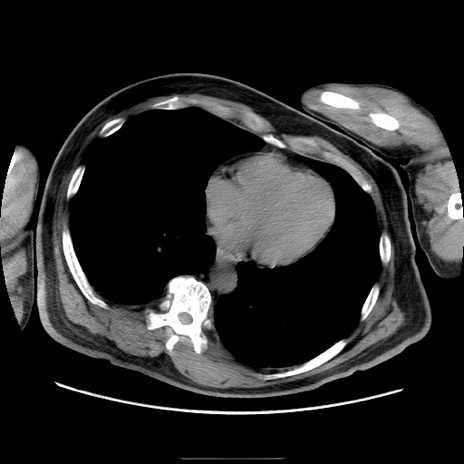

症例

冠状断像